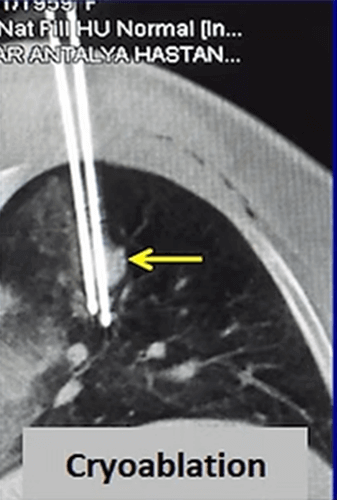

Cryoablation is the newest ablation method in the lung but it is more and more frequently applied for lung cancer. The most important advantages of cryoablation are that it is not painful, can be performed under local anesthesia, can be used in tumors close to the chest wall, the ablation area can be seen as an iceball and larger tumors (> 3cm) can be treated by increasing the number of needles.

In our patient who had a 4x2cm non small cell lung cancer, cryoablation was performed. After the procedure, the 3 and 6 months control CT images show progressive shrinkage of the tumor.